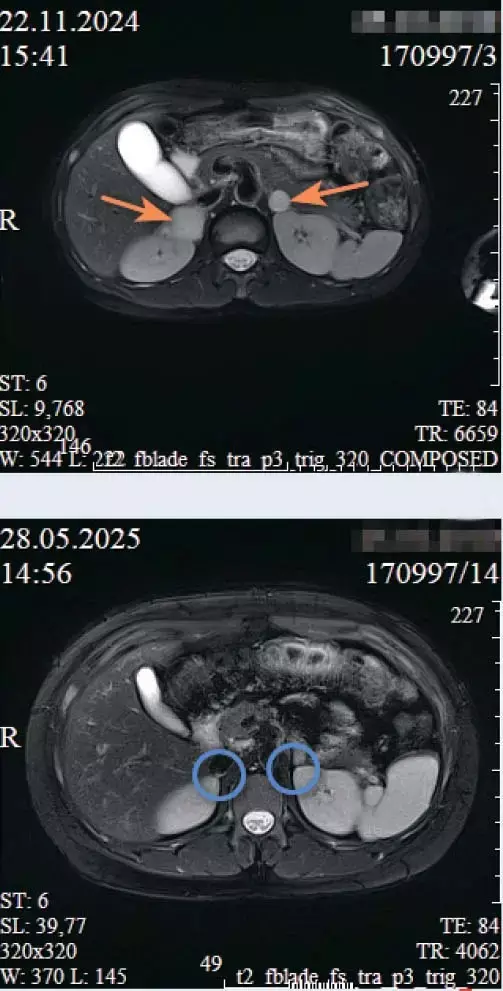

Пациент, 14 лет, экстренно госпитализирован в РНПЦ ДОГИ в тяжелом состоянии после гипертонического криза (АД 240/160 мм рт. ст.), осложненного фокальным судорожным приступом и потерей сознания.

При поступлении сохранялась злокачественная артериальная гипертензия (188/124 мм рт. ст.). КТ и МРТ брюшной полости с контрастированием выявили двусторонние объемные образования надпочечников: справа — солидно-кистозный узел 36×43×55 мм, слева — не менее двух образований до 17 мм. Лабораторно подтвержден гиперкатехоламиновый синдром.

Диагноз: феохромоцитома обоих надпочечников; киста головки поджелудочной железы; вторичная симптоматическая артериальная гипертензия.

В условиях отделения реанимации проведена 14-дневная терапия альфа-адреноблокаторами для стабилизации гемодинамики и профилактики интраоперационного катехоламинового криза. На консилиуме принято решение о необходимости двусторонней адреналэктомии с последующей пожизненной заместительной гормональной терапией.

Выполнена лапароскопическая двусторонняя туморадреналэктомия.

Операция проведена в два этапа:

1) удаление правого надпочечника (в положении на левом боку);

2) удаление левого надпочечника (в положении на правом боку).

Ранний послеоперационный период характеризовался лабильностью гемодинамики с эпизодами артериальной гипертензии, потребовавшей титрования урапидила в условиях отделения интенсивной терапии. Состояние стабилизировалось к 3-м суткам. Послеоперационный период протекал без инфекционных и тромбоэмболических осложнений. Пациент выписан на 15-е сутки в удовлетворительном состоянии.

Двусторонняя феохромоцитома: а) до операции; б) после лапароскопической двусторонней туморадреналэктомии.Контрольные УЗИ и МРТ подтвердили отсутствие объемных образований в ложе надпочечников, что свидетельствовало о радикальности операции. Выявленные неспецифические диффузные изменения паренхимы печени и поджелудочной железы трактовались как следствие перенесенной катехоламиновой интоксикации. Киста головки поджелудочной железы оставалась без динамики, что исключило ее опухолевую природу.

Представленный случай демонстрирует, что лапароскопическая двусторонняя адреналэктомия является высокоэффективным и безопасным методом лечения сложных форм феохромоцитомы у подростков.